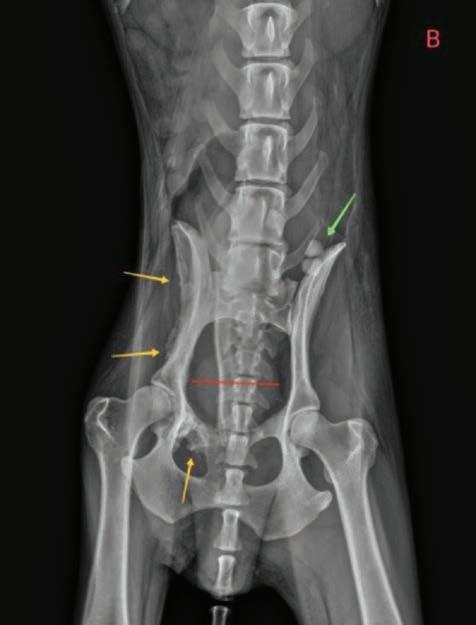

Se realizaron radiografías torácicas y en la proyección lateral derecha se observó, craneal a la silueta cardiaca, una opacidad tejido blando mal definida que producía efecto silueta positivo con esta. La tráquea se visualizó desplazada dorsalmente y el atrio izquierdo aumentado de tamaño. El parénquima pulmonar mostraba un aumento de opacidad en su área caudodorsal, compatible con un patrón pulmonar intersticial no estructurado difuso, el cual se consideró normal debido a que la radiografía fue tomada en fase espiratoria inicial

163

y a la condición corporal del paciente. En la proyección ventrodorsal, el mediastino craneal se observó en el límite superior de tamaño, presentándose un tamaño dos veces superior a la anchura de la vértebra torácica (Fig. 1). Este cambio es compatible con una imagen artefactual secundaria a la leve rotación que presenta la radiografía y a la condición corporal del paciente. El diagnóstico radiológico más probable fue una masa mediastínica craneoventral y cardiomegalia izquierda. En la ecocardiografía transtorácica se confirmó el diagnóstico de enfermedad degenerativa de la válvula

Figura 1. Radiografías torácicas en proyección lateral derecha (A) y ventrodorsal (B) donde se visualiza el área de opacidad de tejido blando craneal a la silueta cardíaca (flechas blancas). En la proyección ventrodorsal se visualiza el mediastino craneal que se presenta en el límite superior de grosor (flechas rojas).